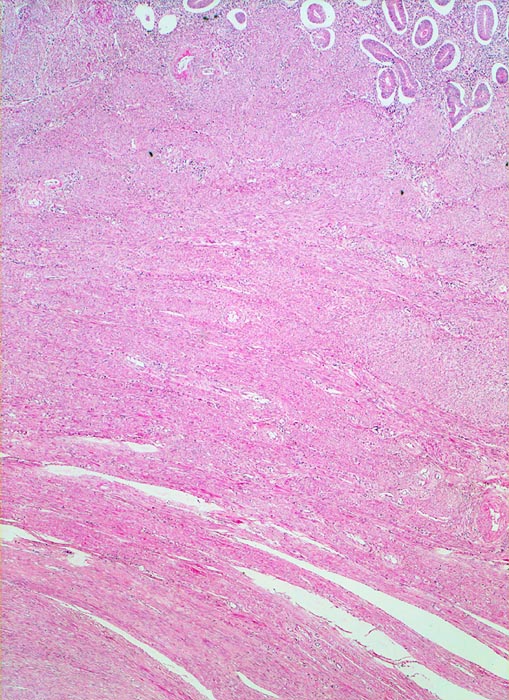

PathoPic – image database / PathoPic ID 4437 - Fibroleiomyom

Fibroleiomyom

benigner Tumor

Uterus

Oben im Bild ist das Stratum basale des Endometriums erkennbar. Die endometranen Drüsen sind von einem artefiziellen Spaltraum umgeben. Daran angrenzend das Myometrium. Im Myometrium ist ein scharf begrenzter unbekapselter glattmuskulärer Tumor erkennbar.

Vergrösserter 258g schwerer Uterus mit multiplen weissen, derben scharf begrenzten, teils intramuralen und teils submukös gelegenen Knoten.

Vaginale Hysterektomie wegen Meno-Metrorrhagien.

Die Drüsen des Stratum basale zeigen während des ganzen Zyklus geringe Proliferationszeichen. Eine Zyklustagbestimmung ist hier deshalb nicht möglich.